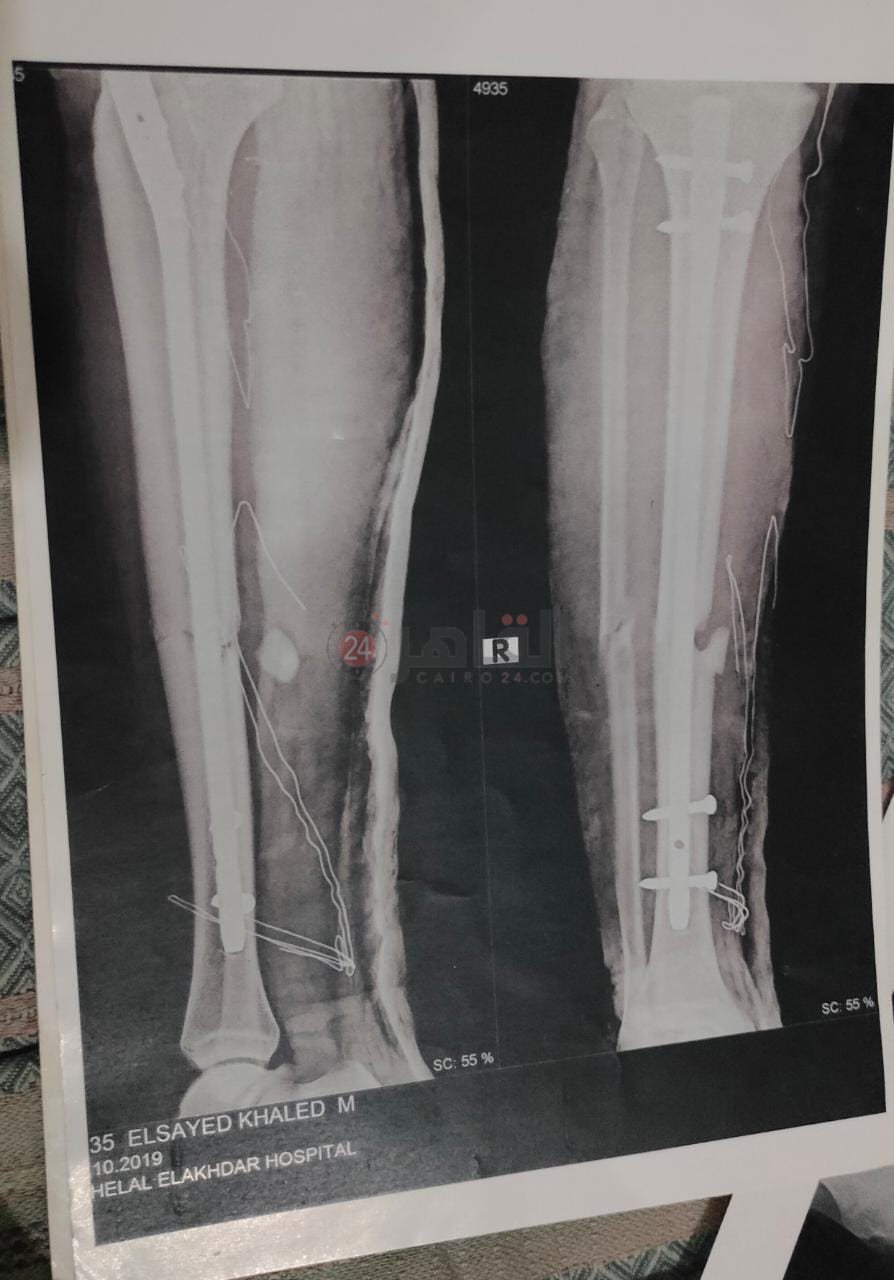

معاناة كبيرة يعيشها اللاعب السيد خالد صلاح، صاحب الـ23 ربيعًا، ابن وكابتن فريق كرة القدم بنادي "الصفوة" الرياضي بمدينة العاشر من رمضان بمحافظة الشرقية؛ بعدما تعرض لإصابة بكسر مضاعف في الساق اليمنى أثناء مباراة مع فريقه، قبل نحو 18 شهرًا، لم يتعافى منها حتى الآن بسبب خطأ طبي وإهمال وتقصير في نواحٍ عدة -على حد وصفه.

وأوضح اللاعب، والذي حملّ شارة القيادة طوال تسع سنوات بفرق كرة القدم بمراحلها السنية المختلفة بالنادي، أن الإصابة التي تعرض لها قبل عام ونصف العام نُقل على إثرها إلى المستشفى المتعاقد معه النادي، والذي طلب عدم ذكر اسمه، قبل أن يشير إلى أن طبيب المستشفى أجرى الجراحة له، لكنه اكتشف فيما بعدْ أن الجراحة تسببت في فقدانه الشعور بساقه، وبعدها، وفور الدخول في مرحلة العلاج الطبيعي مع أحد الأطباء المتعاقد معهم النادي، أصيب من جديد بحرق أسفل قدمه سببه “لمبة العلاج الطبيعي”، تسبب هو الآخر في تأثر أوتار القدم وانكماش أصابعه وعدم عودتها لحالتها الطبيعية من جديد، -وفق حديثه.

وأشار اللاعب، إلى أن أحد الأطباء الكبار، والذي سبق له العمل بالنادي الأهلي، أكد له على أن ما يُعانيه سببه الجراحة الأولى، والتي أخطأ الطبيب فيها بالتسبب في التصاق عظمة الساق بشظية القدم عن طريق ربطهما بمسمار طبي.